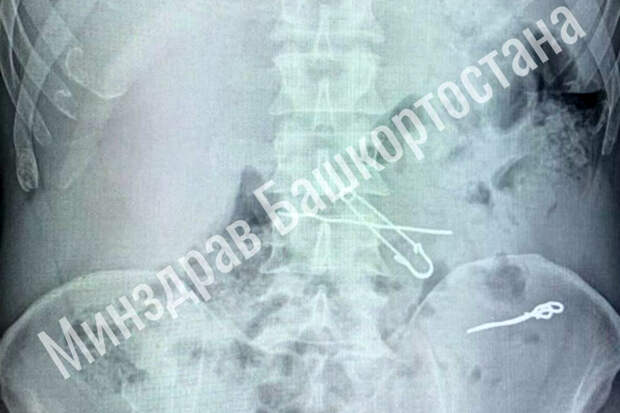

В больницу скорой медицинской помощи поступил мужчина с жалобами на сильные боли в животе. По результатам обследования выяснилось, что у него в толстой кишке находились три металлические скрепки длиной 47, 62 и 90 миллиметров, а в желудке - булавка и проволока.

Пациента срочно госпитализировали в отделение гнойной хирургии, где врачи успешно провели операцию по извлечению всех предметов. Во время вмешательства медики делали контрольные рентгеновские снимки, чтобы убедиться в полном удалении инородных тел. После операции мужчина успешно восстановился и был выписан из медицинского учреждения.